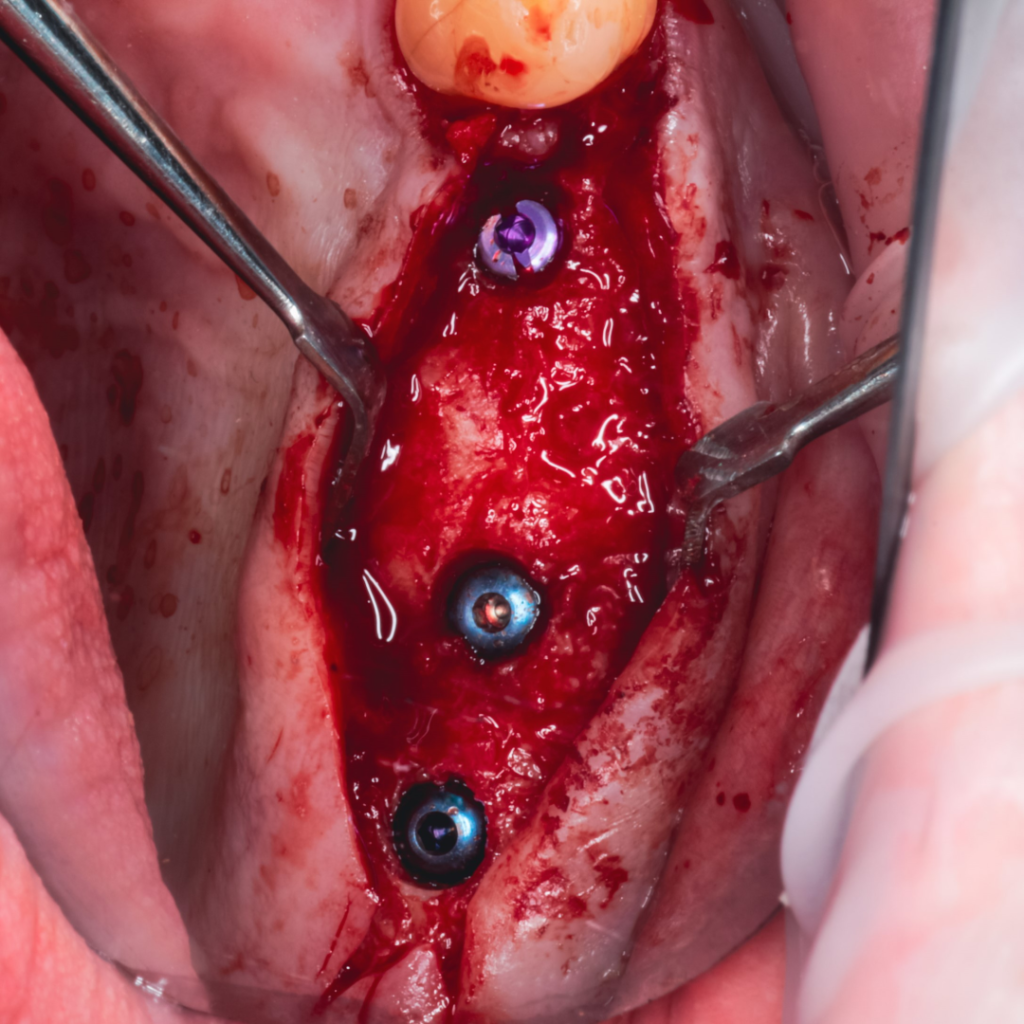

Плановая имплантация в жевательном отделе перед тотальной реабилитацией с поднятием прикуса.

По результатам диагностики принято решение установить имплантаты AnyRidge и AnyOne с использованием хирургических шаблонов Bonepen 3D.